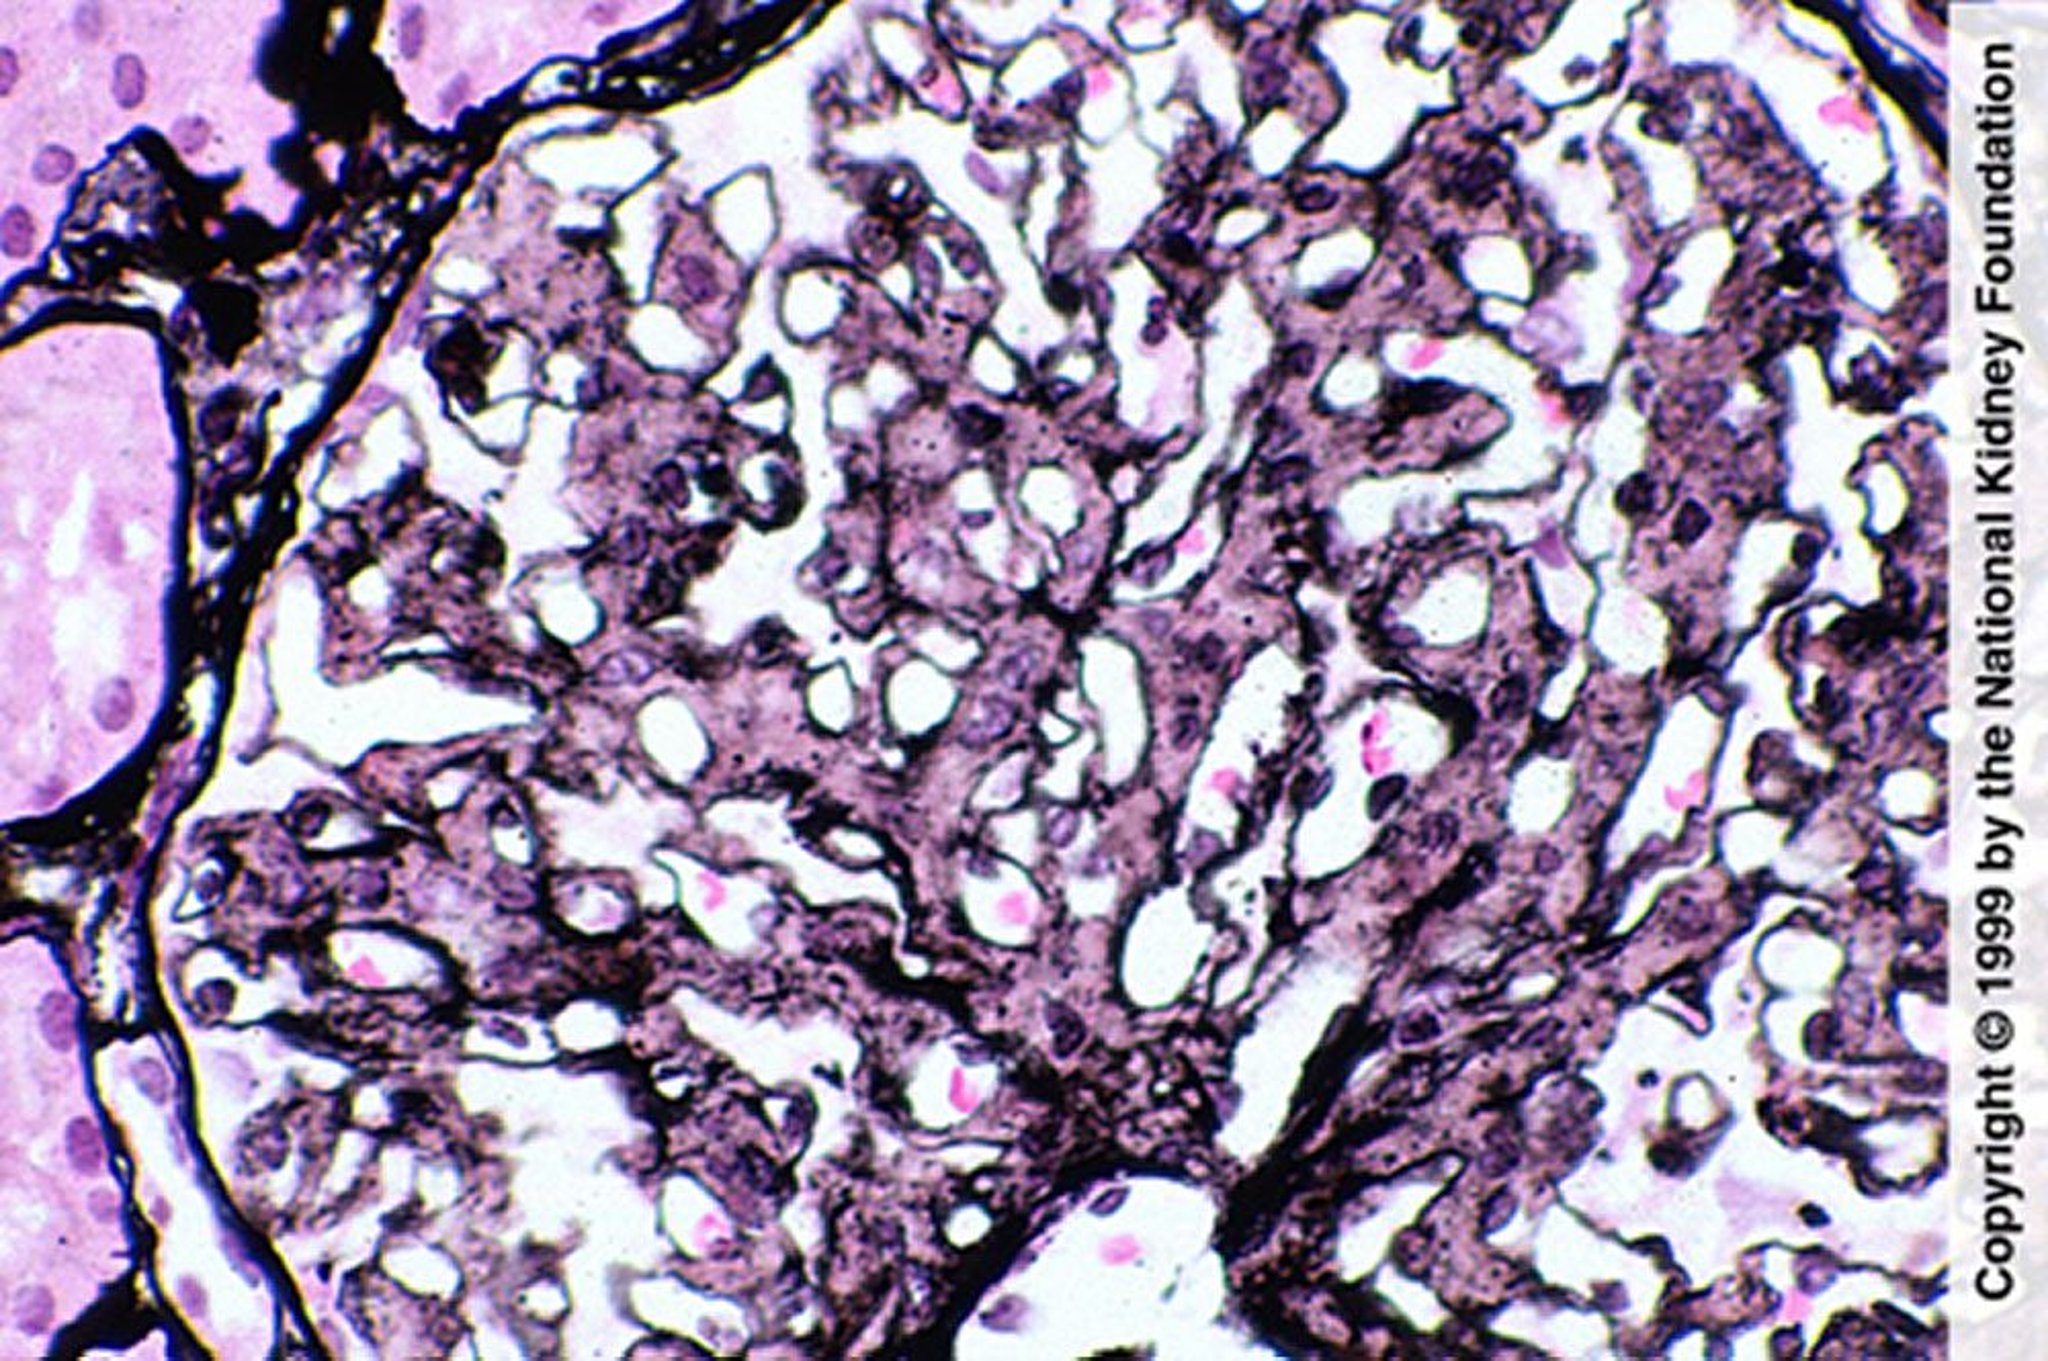

Glomerulopatía fibrilar (proliferación mesangial)

La proliferación mesangial sugiere una glomerulopatía fibrilar; sin embargo, el diagnóstico requiere tinción negativa con rojo Congo, tinción de IgG por inmunofluorescencia y demostración de fibrillas en la microscopia electrónica (tinción de plata de Jones, ×400).

Image provided by Agnes Fogo, MD, and the American Journal of Kidney Diseases' Atlas of Renal Pathology (véase www.ajkd.org).